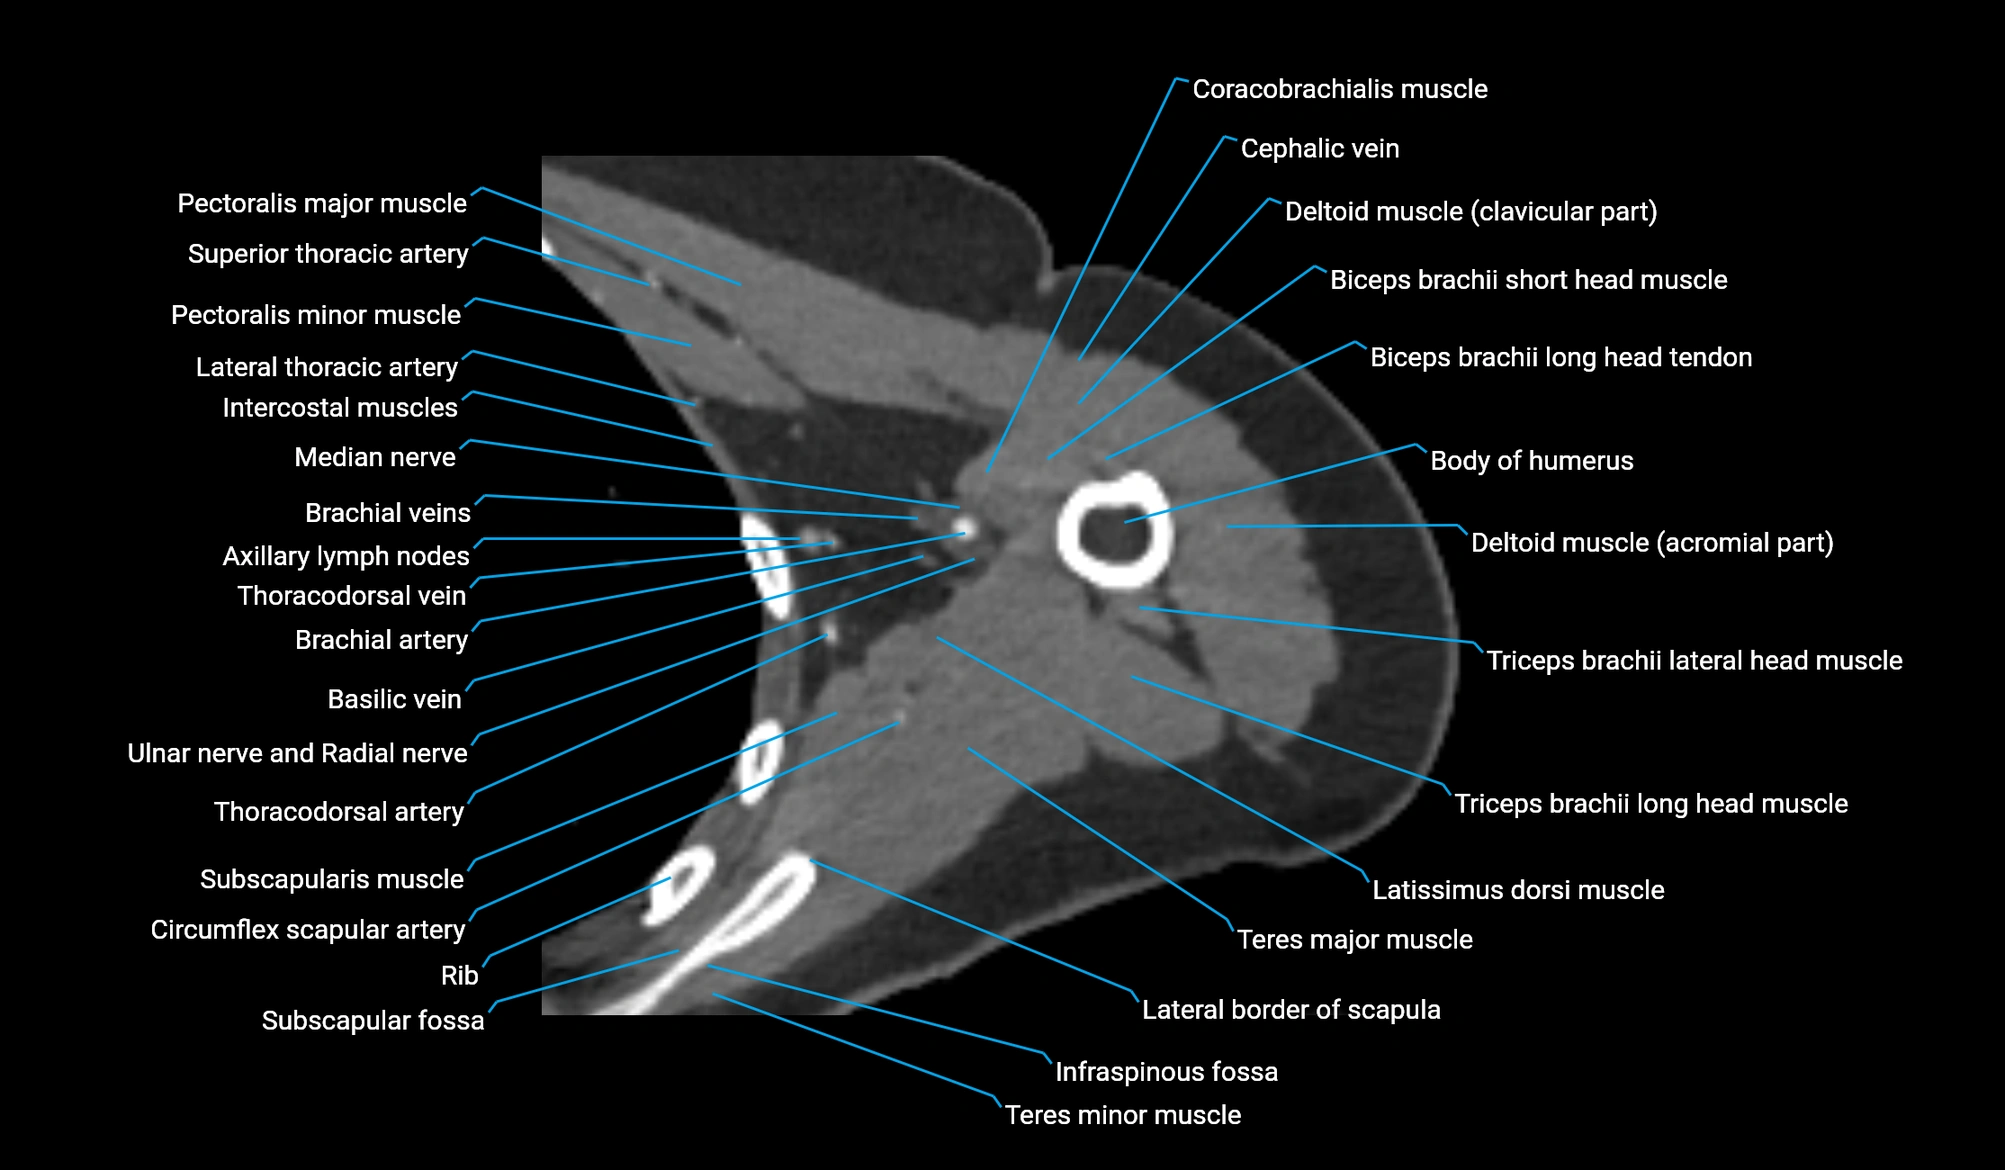

CT image